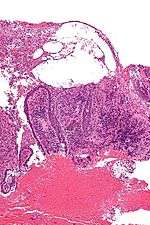

| Micrograph of pemphigus vulgaris with the characteristic "tombstoning". H&E stain. | |

Pemphigus is an autoimmune disease caused by antibodies directed against both desmoglein 1 and desmoglein 3 present in desmosomes. Loss of desmosomes results in loss of cohesion between keratinocytes in the epidermis, and a disruption of the barrier function served by intact skin. The process is classified as a type II hypersensitivity reaction (in which antibodies bind to antigens on the body's own tissues). On histology, the basal keratinocytes are usually still attached to the basement membrane leading to a characteristic appearance called "tombstoning." Transudative fluid accumulates in between the keratinocytes and the basal layer (suprabasal split), forming a blister and resulting in what is known as a positive Nikolsky's sign. This is a contrasting feature from bullous pemphigoid, which is thought to be due to anti-hemidesmosome antibodies, and where the detachment occurs between the epidermis and dermis (subepidermal bullae). Clinically, pemphigus vulgaris is characterized by extensive flaccid blisters and mucocutaneous erosions. The severity of the disease, as well as the mucosal lesions, is believed to be directly proportional to the levels of desmoglein 3. Milder forms of pemphigus (like foliacious and erythematoses) are more anti-desmoglein 1 heavy.